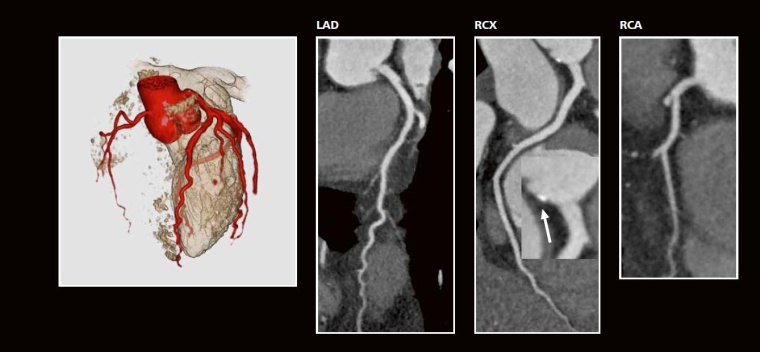

Fall 2

Anamnese:

40-jähriger Mann, Architekt. Bei Stress auf den Baustellen deutlich körperliches Unwohlsein. Postprandial oft „Herzbeschwerden“ (DD: Roemheld-Syndrom). 182 cm, 80 kg, 1x/Woche Badminton, Patient möchte gerne wieder joggen, sorgt sich aber um das Herzinfarktrisiko.

Kardiovaskuläre Risikofaktoren:

bekannte arterielle Hypertonie, kein Nikotin, kein Diabetes, positive Familienanamnese: Großvater mütterlicherseits 2x Myokardinfarkt mit < 60 Jahren, Cousin mütterlicherseits Myokardinfarkt mit 45 Jahren, keine bekannte Fettstoffwechselstörung! Blutdruck in Ruhe: 120/80 mmHg (mit ACE-Hemmer), schwere (familiäre) Dyslipoproteinämie: Gesamt-Cholesterin: 320 mg/dl, LDL-Cholesterin: 201 mg/dl, HDL-Cholesterin: 63 mg/dl, Triglyzeride: 281 mg/dl, Harnsäure: 7,3 mg/dl.

CT -Angiographie:

Linksversorgungstyp mit sehr klein angelegter RCA (3D-Bild). In der multiplanaren Rekonstruktion (Curved MPR) Ausschluss von kalzifizierten und nicht-kalzifizierten arteriosklerotischen Plaques. Aber diskrete Kalzifikation in der Aortenwurzel (Vergrößerung Mitte, Pfeil) als Beweis einer beginnenden Arteriosklerose in sehr jungem Alter. Strahlendosis CTA = 1,8 mSv.

Therapie:

Beruhigung hinsichtlich eines akuten oder mittelfristigen Herzinfarktrisikos bei jedoch erhöhtem Lebenszeitrisiko! Intensive Senkung des LDL-Cholesterins mit einem Statin. Gesunde Ernährung, regelmäßig Sport, regelmäßige Blutdruckkontrolle, Stress-Bewältigung.